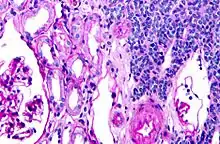

| Micrograph of a metanephric adenoma with structures reminiscent of those seen in papillary renal cell carcinoma. H&E stain. | |

Metanephric adenoma is diagnosed histologically. The tumours can be located at upper pole, lower pole and mid-hilar region of the kidney; they are well circumscribed but unencapsulated, tan pink, with possible cystic and hemorrhagic foci. They show a uniform architecture of closely packed acinar or tubular structures of mature and bland appearance with scanty interposed stroma.[3][4][5][6][7] Cells are small with dark staining nuclei and inconspicuous nucleoli. Blastema is absent whereas calcospherites may be present. Glomeruloid figures are a striking finding, reminiscent of early fetal metenephric tissue. The lumen of the acini may contain otherwise epithelial infoldings or fibrillary material but it is quite often empty. Mitoses are conspicuously absent.[3][4][5][6][7] In the series reported by Jones et al. tumour cells were reactive for Leu7 in 3 cases of 5, to vimentine in 4 of 6, to cytocheratin in 2 of 6, to epithelial membrane antigen in 1 of 6 cases and muscle specific antigen in 1 of 6.[8] Olgac et al. found that intense and diffuse immunoreactivity for alpha-methylacyl-CoA racemase (AMACR) is useful in differentiating renal cell carcinoma from MA but a panel including AMACR, CK7 and CD57 is better in this differential diagnosis.[9] Differential diagnosis may be quite difficult indeed as exemplified by the three malignancies initially diagnosed as MA that later metastasized, in the report by Pins et al.[10]